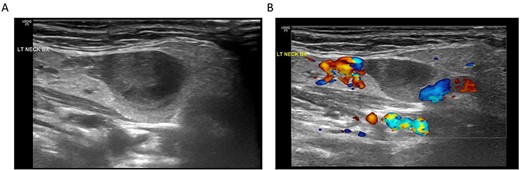

The patient has a history of long-standing hypertension managed with enalapril and amlodipine. She also has hyperlipidemia which is managed with diet modification. On the day of the encounter, her vital signs were within normal range besides a mildly elevated blood pressure reading of 161/88 mmHg. Her physical examination and laryngoscopy were unremarkable, except for fullness on the left submandibular neck, without palpation of distinct masses or nodules. The discrepancy between physical examination and imaging prompted additional workup with an ultrasound (US) of the neck and request for fine-needle aspiration of the reported left submandibular neck mass. During the pre-intervention US, the vascular nature of the lesion was confirmed (Fig. 2). After real-time US evaluation by the interventional radiologist and further review of the prior neck CT, it was thought the lesion was most consistent with a venous aneurysm arising from the left external jugular vein at the level of the submandibular gland.

(A) Ultrasonography of the submandibular neck lesion; (B) ultrasonography of the lesion with color Doppler; the apparent lack of flow within the venous aneurysm is likely related to the imaging technique and relatively slow flow within the aneurysm compared to the adjacent external jugular vein.